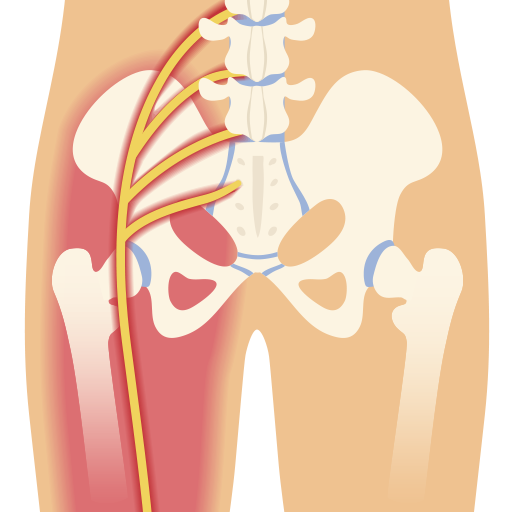

Anatomía y función del nervio ciático

El nervio ciático es el nervio más largo del cuerpo humano. Se origina en la región lumbar de la columna vertebral, específicamente a partir de las raíces nerviosas que surgen de la médula espinal en los niveles L4, L5, S1, S2 y S3. Este nervio se extiende desde la parte baja de la espalda, atravesando los glúteos y descendiendo por la parte posterior de cada pierna, dividiéndose en ramas que llegan hasta la planta del pie y los dedos.

Su función es clave para la movilidad y la sensibilidad de la parte posterior y lateral de las piernas. Debido a su longitud y a las diversas trayectorias que recorre, el nervio ciático puede estar sujeto a compresión o irritación en diferentes puntos, provocando síntomas asociados con la ciática.